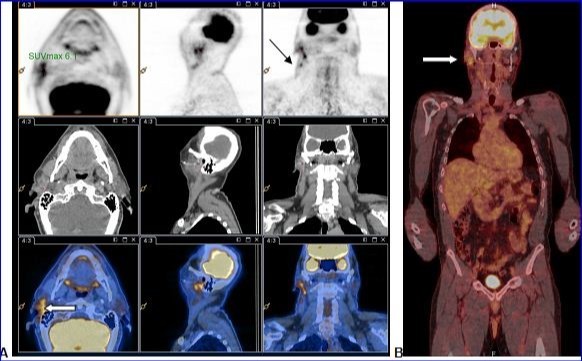

PET-CT with 18F-FDG injection of iodinated contrast post surgery showed an intense and diffuse hyper metabolism at the surgical site in the right parotid and discreetly moderated hypermetabolic lymph nodes in the ipsilateral lymph nodes areas II and III. No morphological or metabolic argument for tumor was demonstrated (either primary or secondary) on the whole-body (Figure 2).

Figure 2.A and B: PET-CT with 18F-FDG injection of iodinated contrast showed: A.Intense and diffuse hyper metabolism at the surgical site in the right parotid (large white arrow) and discretely hypermetabolic lymph nodes in the ipsilateral lymph nodes areas II and III (thin black arrow). B. Lack of morphological or metabolic arguments for primary or secondary manifestation of malignant melanoma of the others structures examined.